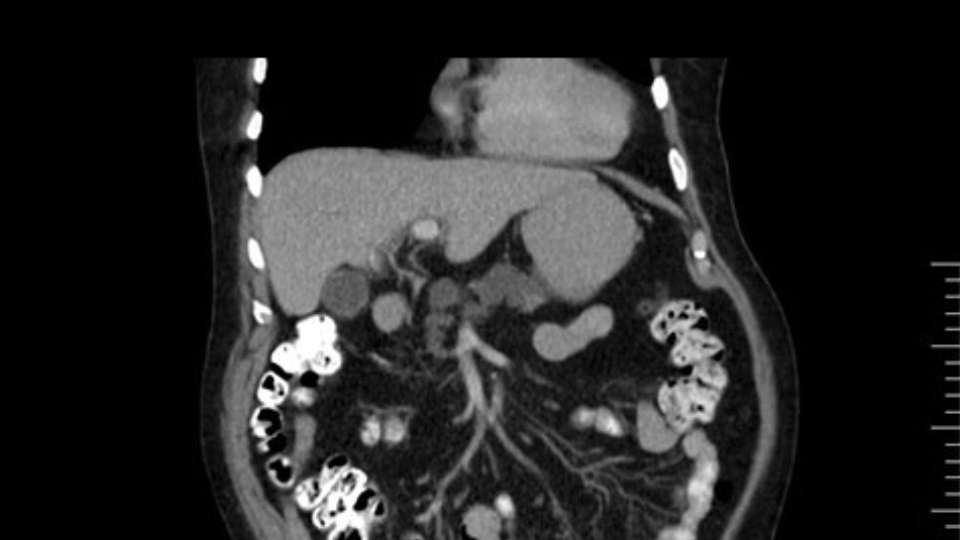

He has no liver metastases or obvious metastatic disease. On reviewing his CT scan, he has normal vascular anatomy; he has no involvement of the portal vein by the looks of it, or the superior mesenteric vein.

The next item that I would look at: the issue would be the vessels and usually start at the portal vein, watch the portal vein, follow it down, down-down-down to the neck of the pancreas - which is here - and there’s no impingement by tumor, which is great. The SMV and the splenic vein, which is here. The splenic vein junction is normal, which is great.

The other thing I look at is the gastroepeiploic arcade- which is this thing here- which is where the gastroepeiploic vein joins the portal vein. I call it the gateway to the neck of the pancreas because you pretty much have to divide it to get to the neck. The middle colic vein usually drains either into it or nearby. I think we’re seeing it here. Again,that can be divided and I usually divide those two and it helps me get under the neck. Again, there’s no issues here with the tumor so it’s nice from that perspective. If I was concerned about the vein, which I’m not here, I would go to the coronal view. It’s a nice way to look at the vein on just a couple of cuts and you can see a beautiful view of it here. There’s the portal vein, there’s the head of the pancreas. There’s the tumor. It’s a little closer here than it looks on the other one. I doubt it’s involved. If it’s touching, it may not be invading it but even if it was, it's a short segment. Anyways, there’s the SMV there’s the splenic vein, and everything looks good. You can see the stent. I ignore the stent. It’s the most dramatic looking thing in the picture but it’s actually the least important.

The next thing we always evaluate, although we do not expect invasion to the portal veins in this case, we must always trace the path of the portal vein, in both directions, from top to bottom. The splenoportal confluence and the superior mesenteric vein, which in this case does not appear to be compromised.

Por otro lado, siempre evaluamos -aunque en este caso no esperamos que haya invasión de los vasos portales-, siempre hay que hacer el recorrido de la vena porta, en ambos sentidos, de arriba hacia abajo; el confluente esplenoportal y la vena mesentérica superior, que en este caso no aparentan estar comprometidos.